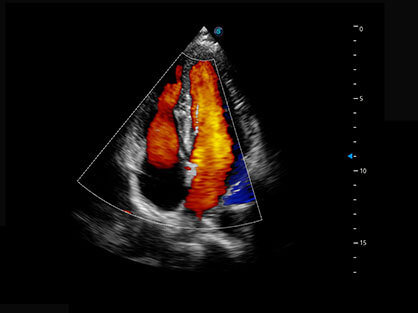

作为P系列家族成员之一,P40 Plus采用玖鼎集团高端超声系统平台——极光,并以时尚秀丽、小巧灵动的外观设计绽放出灵动之韵、科技之美。高端平台的使用保证了P40 Plus优质的基础图像;完备的高级功能可满足您全身应用的基本需求;丰富的探头配置、多样的高级4D成像及分析软件为您日益增多的妇产应用需求提供丰富的诊疗方案。

结合玖鼎集团超宽频带探头技术优势,能够更好地获得高分辨力与高穿透力的平衡,保证图像质量,为临床诊断保驾护航。

微米成像技术提升了对组织斑点噪声信号的抑制能力,并进一步强化边界信息,从而获得清晰图像。